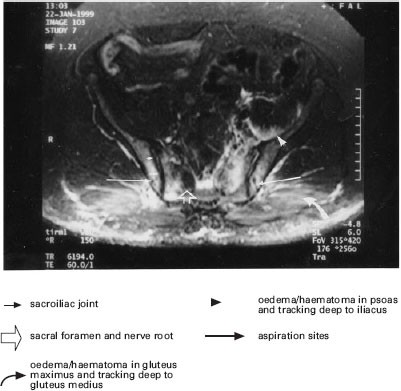

Sciatic Nerve Compression Following Bone Marrow Harvest Bone Marrow Transplantation